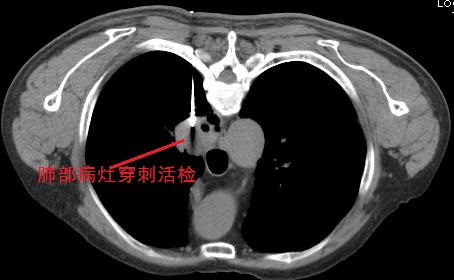

肺癌CT诊断后的穿刺活检还有意义?

这个问题其实需要个性化分析。既然两种方法各有所长,那相结合应用,自有它的道理,不能说是完全重复。比如说,假如CT已经诊断为肺癌,但对其具体类型仍然没有把握,影响到后续的治疗方案制定,那么,进行肺穿刺取活检标本,送病理学检查,还是有必要的。

至于是不是对CT所诊断的肺癌,都要做肺穿刺,那就需要医患双方根据具体情况好好沟通协商了。比如,有些病例完全可以在CT诊断后直接微创手术切除后,再送病理检查确诊,也是一种选项。

CT引导下穿刺活检,对病灶性质确诊意义大